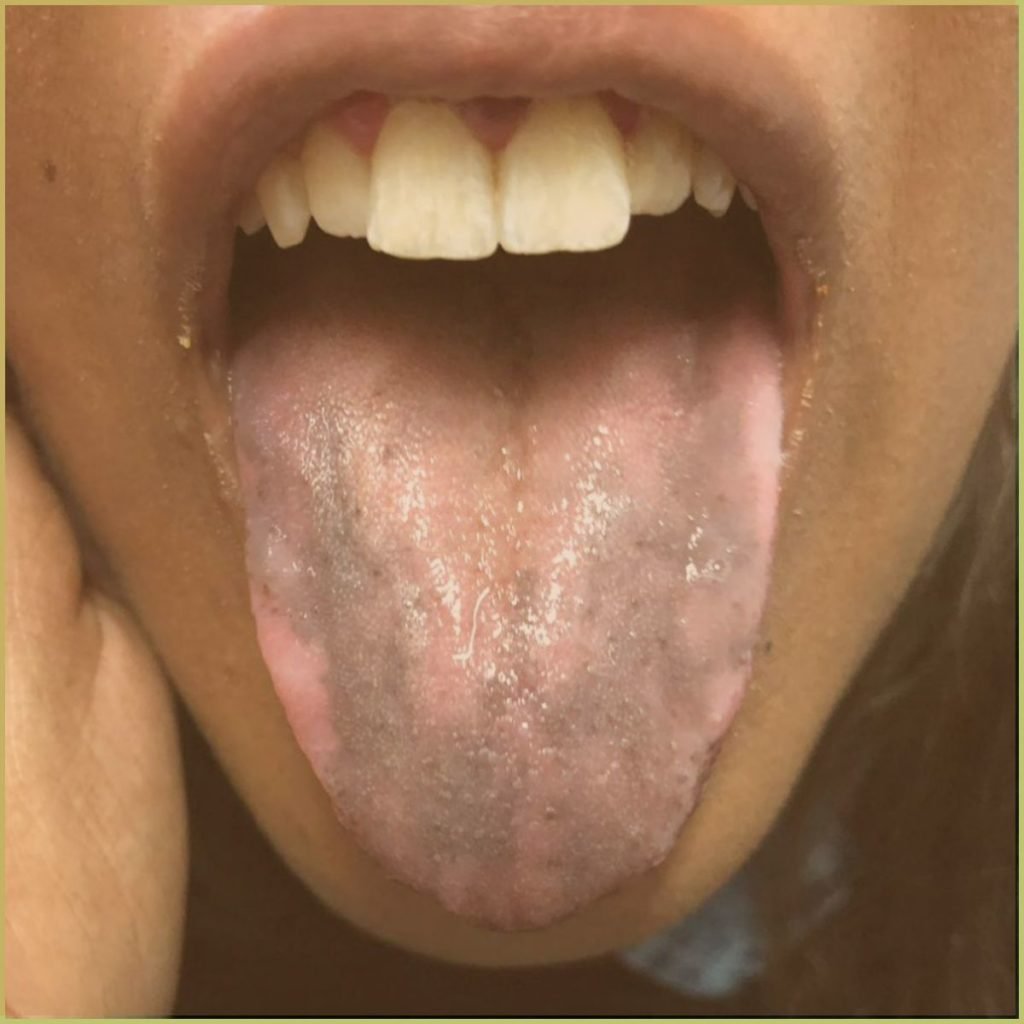

ADDISON'S DISEASE

Addison’s Disease (primary adrenal insufficiency) is a rare autoimmune endocrine disorder that leads to improper steroid hormone production. Recall, cortisol and aldosterone are fabricated in the adrenal cortex. Secondary adrenal insufficiency is caused by decreased production of adrenocorticotropic hormone (pituitary gland) or corticotropin-releasing hormone (hypothalamus). When stressed an inadequate production of adrenal hormones may lead to a potentially serious medical emergency (adrenal crisis). Adrenal insufficiency may also be triggered by infection (tuberculosis, histoplasmosis, coccidioidomycosis), medications (ketoconazole, rifampicin, phenytoin), sepsis, or trauma to the adrenal glands. Visual changes to the skin and oral mucosa are due to secondary melanocyte stimulation by increased levels of adrenocorticotropic hormone (ACTH) or β-lipotropin. The common clinical presentation includes:

- Brown macular pigmentation is usually seen in association with cutaneous bronzing.

Addison’s disease is confirmed using serological testing. Adrenal hormone levels will remain low after stimulation with synthetic ACTH. Diagnosis is based on the lesion history, clinical presentation and microscopic findings, which may include melanosis visible within mucosa biopsy. Your differential diagnosis should include: